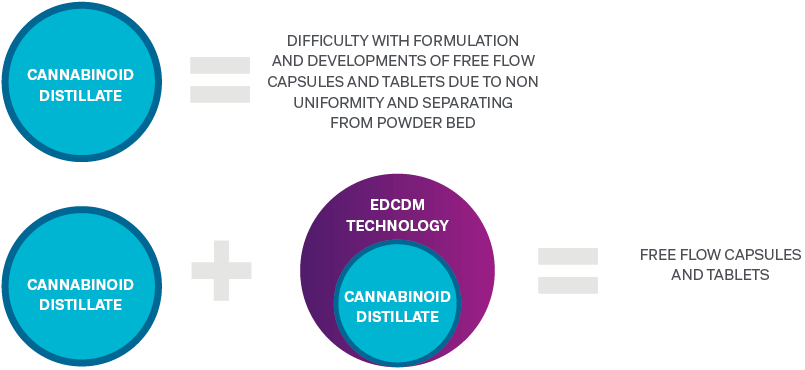

Enhanced Distillate Capture and Dissolution Matrix (EDCDM) technology

Zelira has successfully developed and demonstrated enhanced dissolution of cannabinoids using its enhanced distillate capture and dissolution matrix (EDCDM)

Before this breakthrough technology was developed by Zelira cannabis manufacturers had difficulty in formulating and developing free flow solid oral dosage forms based on cannabinoid distillate. This is due to the non-uniformity of cannabinoid distillate and its separation from the powder bed. EDCDM technology, developed by Zelira, resolves this problem by creating the capacity to capture distillate in a unique and proprietary matrix. When combined with the cannabinoid distillate, it creates a free-flowing powder base for capsules and tablets.

Enhanced Distillate Capture and Dissolution Matrix (EDCDM)

This novel matrix absorbs the distillate into a nano porous silicate particle where the distillate is effectively trapped in the structure of the silicate rendering the powder bed dry. As a result, this prevents the distillate from separating from the powder bed during encapsulation and under the compression forces utilised in tableting thus opening new ways to develop pharmaceutical grade, cannabinoid-based medicines in solid oral dosage forms such as capsules and tablets.